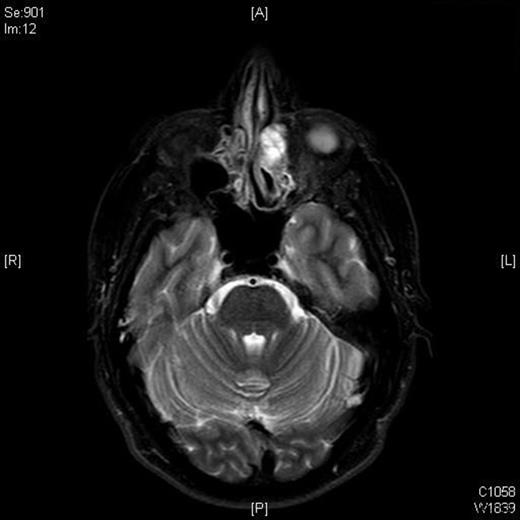

A follow-up MRI scan in 2009 showed contrast-enhancing soft tissue abnormalities within both of the frontal sinuses and the left ethmoid sinus (Figures 1 and 2). A CT scan showed soft tissue abnormalities in these locations (Figure 3). An incisional biopsy confirmed a subepithelial ameloblastoma.